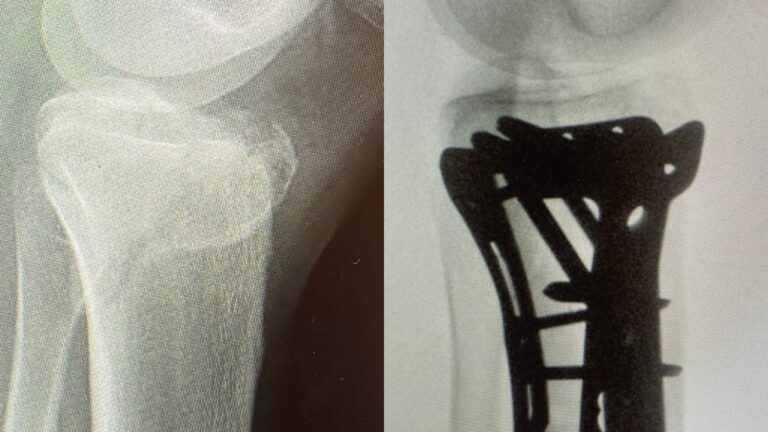

Polven

alueen murtuma

Ennen – jälkeen